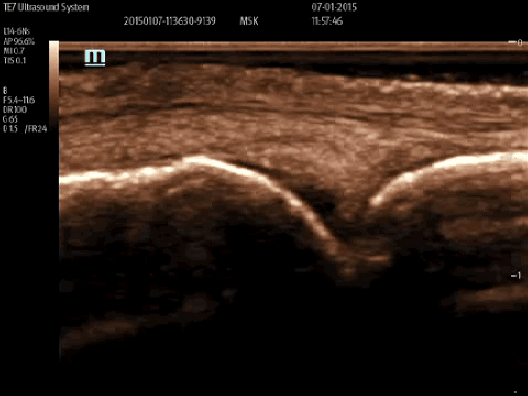

iNeedle

Dla głowic liniowych i convex dostępna jest funkcja zaawansowanej wizualizacji igły iNeedle. Technologia ta znacznie poprawia obraz igły podczas procedury In-Plane (kłucia w płaszczyźnie obrazowania).